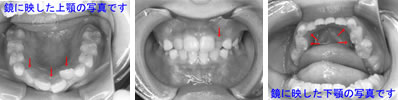

一見すると、あまり難しい反対咬合には見えませんが、実は下あごを無理に後ろに押し下げている状態で普段過ごしています。そのため、顎の関節に不具合が生じていました。

また、上顎には一部乳歯が残っているのですが、もう抜けそうになっていたので、その隙間をどうするかも問題となっていました。それに加え、上顎の2番目の永久歯(側切歯)が通常より幅が狭い「矮小歯」だったので、隙間が開いているなどの問題も重なっていました。

さまざまな問題をふくんでいたので、最新のCAD技術を応用した矯正治療分析ソフトを用いて治療計画を立てて、動画で治療経過予測を説明しています。